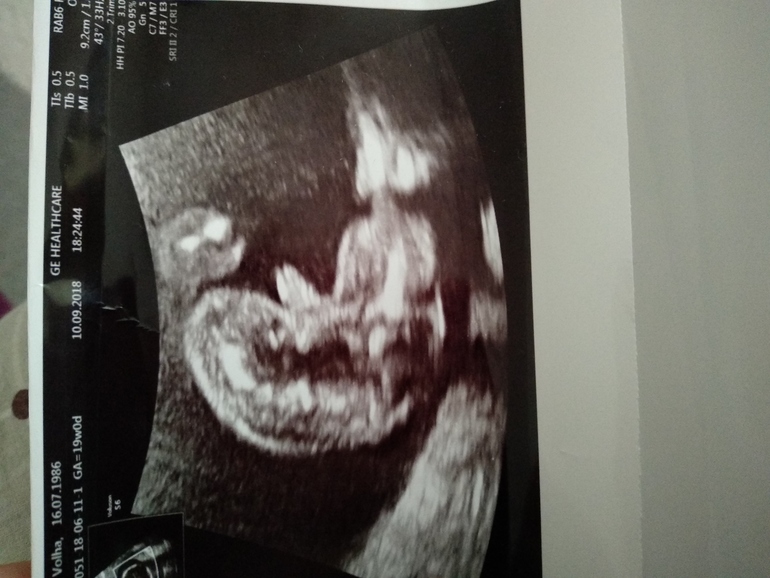

Круглый животик, маленькая грудная клетка - к девочке. У меня совпало. У сына грудная клетка была выше животика, у дочки наоборот. Ну у дочки и половой бугорок был виден на УЗИ. И, если это бугорок, то по нему тоже девочка.

Девочка ) судя по наклону . Я фотки нашла в интернете как отличать . Мне кажется девочка )) но я так чисто угадываю - не специалист

Сейчас с учётом аппаратуры, мальчика в 12 недель видят многие. Мне Ефимова в Середавина в 12 недель ничего не сказала , итог дочка.Всем кого знаю если и говорили пол, то мальчишки были. А на фото мне кажется, что только ножки видно